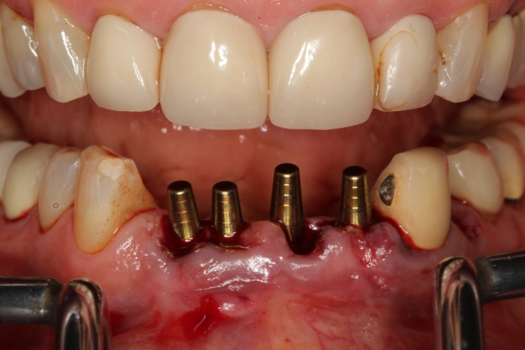

On the day of surgery, the plan was to extract teeth Nos. 21, 23, 24, 25, and 26, place 3.0 x 13-mm implants in the anterior region due to limited spacing, and place a 4.1 x 10-mm implant in the No. 21 extraction site. Before the extractions were performed, the No. 23 pontic was sectioned from the existing 2-unit cantilevered bridge utilizing ceramic and metal high speed rotary cutting burs ZR 6881 and H34L (Komet-USA), respectively. After removal of the pontic and extractions, the surgical guide was verified to be seating positively (Figure 36 through Figure 38). Surgical guide protocol was followed, and all implants were successfully placed and torqued to a value of greater than 35 Ncm (Figure 39 and Figure 40). All implants were placed without flapping, with the exception of No. 23. The flap was elevated to reposition lingual keratinized tissue facially for enhanced esthetic tissue profile. The implants were then prepared with a high-speed carbide bur (Komet-USA) with copious amounts of water (Figure 41 and Figure 42). The one-piece 3.0-mm diameter implant served the needs of the patient's spacing requirements. Inter-occlusal space requirements and path of draw were verified. The PMMA provisionals were air abraded and relined with crown-and-bridge material (Figure 43 through Figure 45).

Fig 41. Abutment preparation.

Figure 41

Fig 42. Occlusal view of prepared implants.

Figure 42